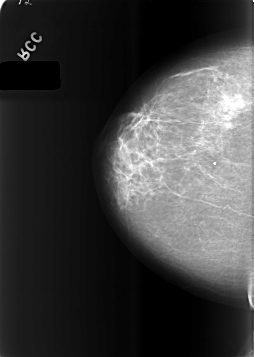

C_0483_1.RIGHT_CC

RIGHT_CC LINES 5712 PIXELS_PER_LINE 4080 BITS_PER_PIXEL 12 RESOLUTION 50 NON_OVERLAY